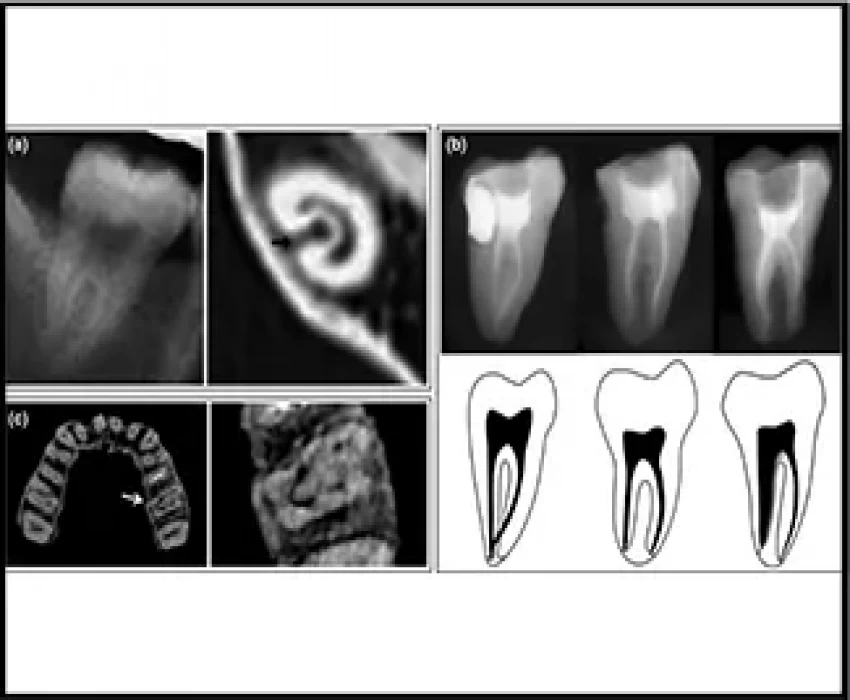

Whereas the skills and knowledge of the endodontist are paramount for successful root canal treatment, radiographic analysis is important for determining canal morphology. Cone-beam computed tomography (CBCT) and micro-CT can accurately determine root canal morphology. CBCT has the ability to overcome the limitations of conventional radiography such as three-dimensional evaluation of the complex canal anatomy during endodontic treatment. However, CBCT and micro-CT are not always feasible.

Combined X-ray analyses, however, such as performing the buccolingual view for identification of canal bifurcation and canal continuity, may increase the accuracy of identifying complex root canal morphology.

- large canal becoming less obvious may logically determine there is a bifurcation;

- large canal becoming thinner and deviating towards one side, there may be one small and

- one large canal or furcated roots, and may logically determine that there is a bifurcation;

- medium root canal, gradual tapering, cannot logically determine that there are two canals but the proximal view may display a second root canal;

- buccolingual view shows a direct bifurcation.